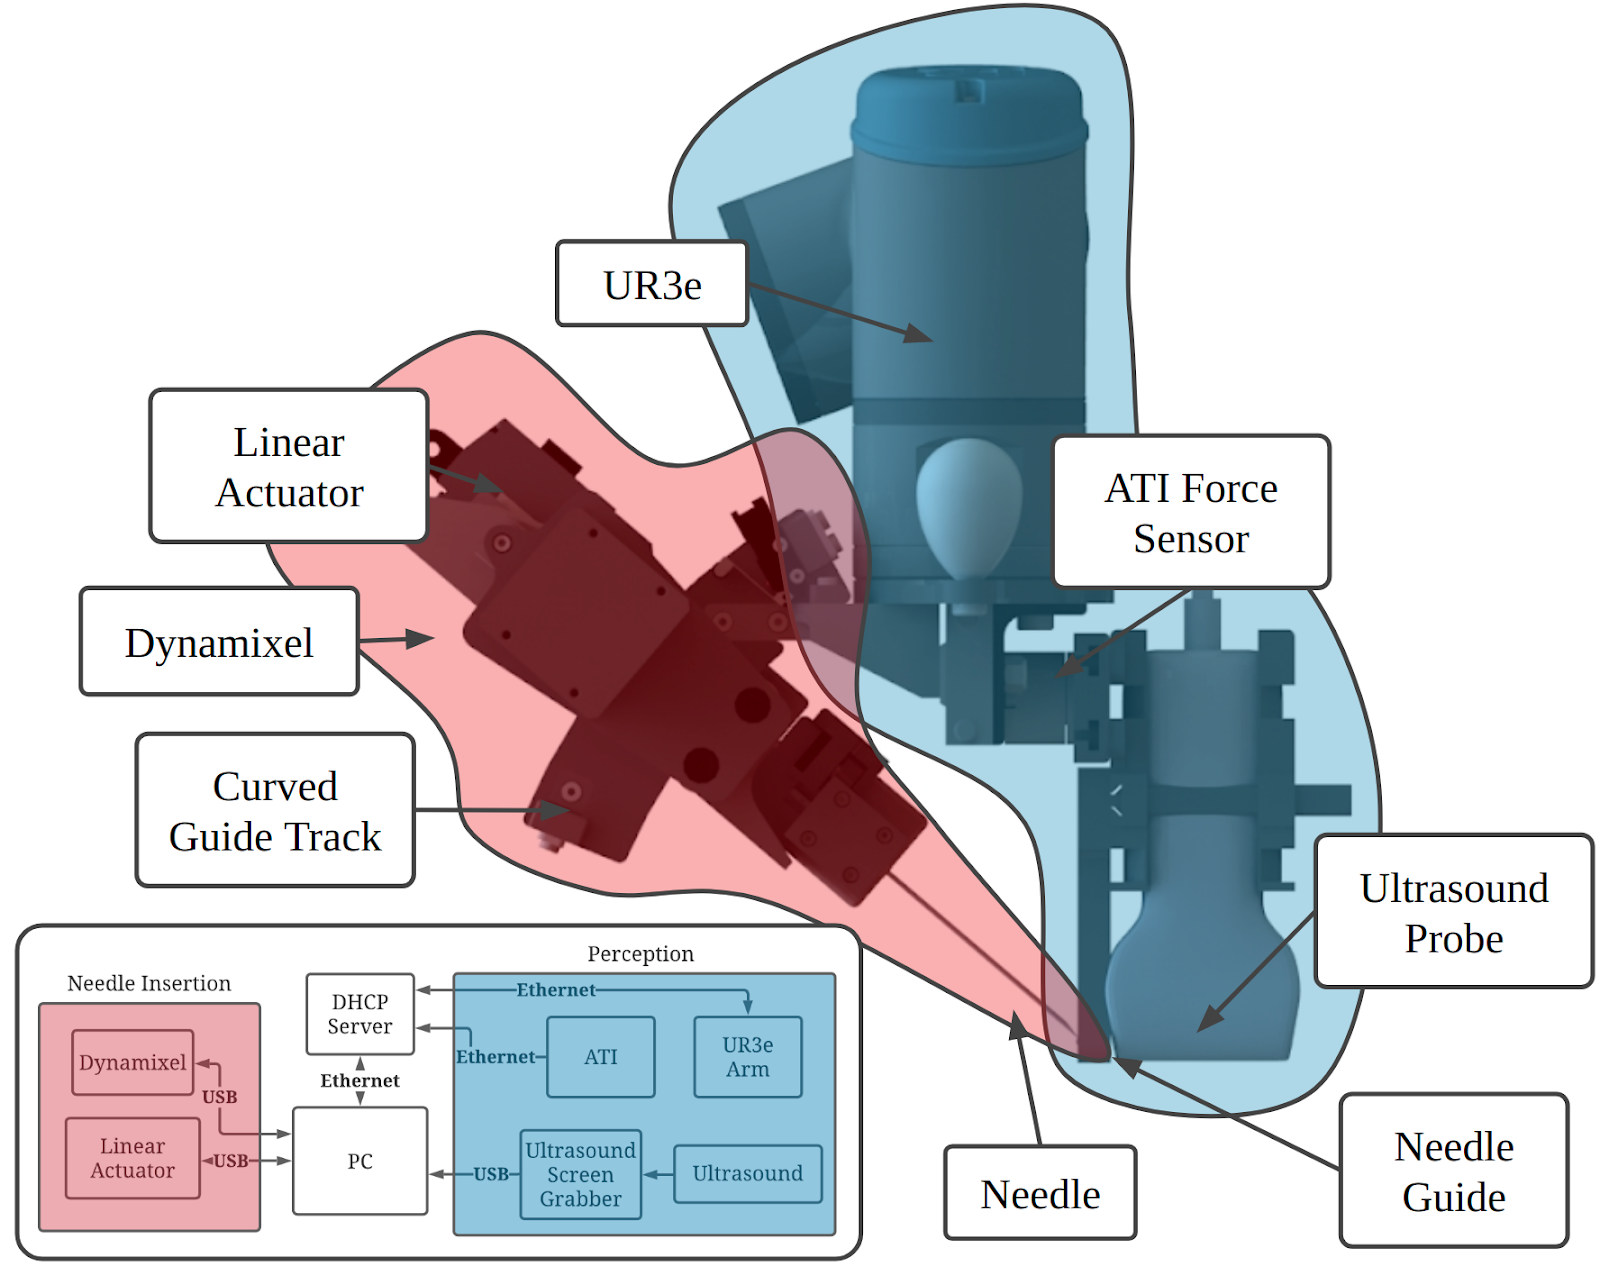

Our system for teleoperated needle insertion, as seen in Fig. 1, aims to mechanize the Seldinger Technique. It can be broken down into two major components highlighted in Fig. 3:

-

1.

Ultrasound scanning (blue): an ultrasound probe, robot arm, and force sensor for ultrasound based perception.

-

2.

Needle Insertion (red): a linear and angular actuator for needle insertion.

III-A Hardware

In practice femoral access is a multi handed, sometimes multi-physician task. This can pose many issues in the field of robotics where coordination between robotic systems can be very computationally expensive. To reduce the amount of manipulation and robotic degrees of freedom required we designed our hardware around single-manipulator approach. This decision has led us to the design seen in Fig.3, where both perception and insertion occur using the same manipulator.

The major sections of the mechanism can be broken down into its two functionalities:

III-A1 Ultrasound Scanning (blue)

To gain subdermal information a Fukuda Denshi portable point-of-care ultrasound scanner was attached to a UR3e arm. Due to the workspace constraints of the UR3e arm the probe was mounted vertically giving the system the greatest amount of manipulatibity through the smallest possible form factor.

We incorporated a 6 axis ATI Nano25 force sensor which fits between the ultrasound probe and the UR3e arm. Using isolated force feedback which only measures force along the ultrasound probe leads to better, more accurate ultrasound scanning.

III-A2 Needle Insertion (red)

The second half of the mechanism relates to insertion control. The main component on this side is the PA-12-22017512R linear actuator and angular degree of freedom. The angular degree of freedom consists of a belt-driven carriage on a curved guide track actuated by a M42P-10-S260-R dynamixel motor. The curve of the guide track was designed to rotate around the point of needle insertion to adjust the needle’s angle with respect to the surface of the skin.

The other major component of the insertion mechanism is the needle guide which helps keep the needle aligned with the plane of the ultrasound image during insertion.

III-B Data streams

In total the system contains 3 forms of actuators: (i) the PA-12 Linear actuator used for needle insertion, (ii) a dynamixel motor to control the angular dof which are commanded and give feedback over USB, and (iii) a UR3e robotic arm which is controlled through Ethernet. The ultrasound images are collected through an AV.io HD screen grabber which converts the S-video output of the ultrasound machine to video over USB. The ATI sensor gives force feedback over ethernet. All of these data streams are passed into a PC which converts them to time stamped ROS topics used for central data collection and control. The data diagram for the system can be found in Fig. 3.